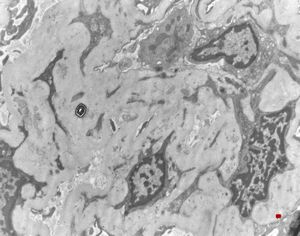

M,22y. | type II membranoproliferative glomerulonephritis